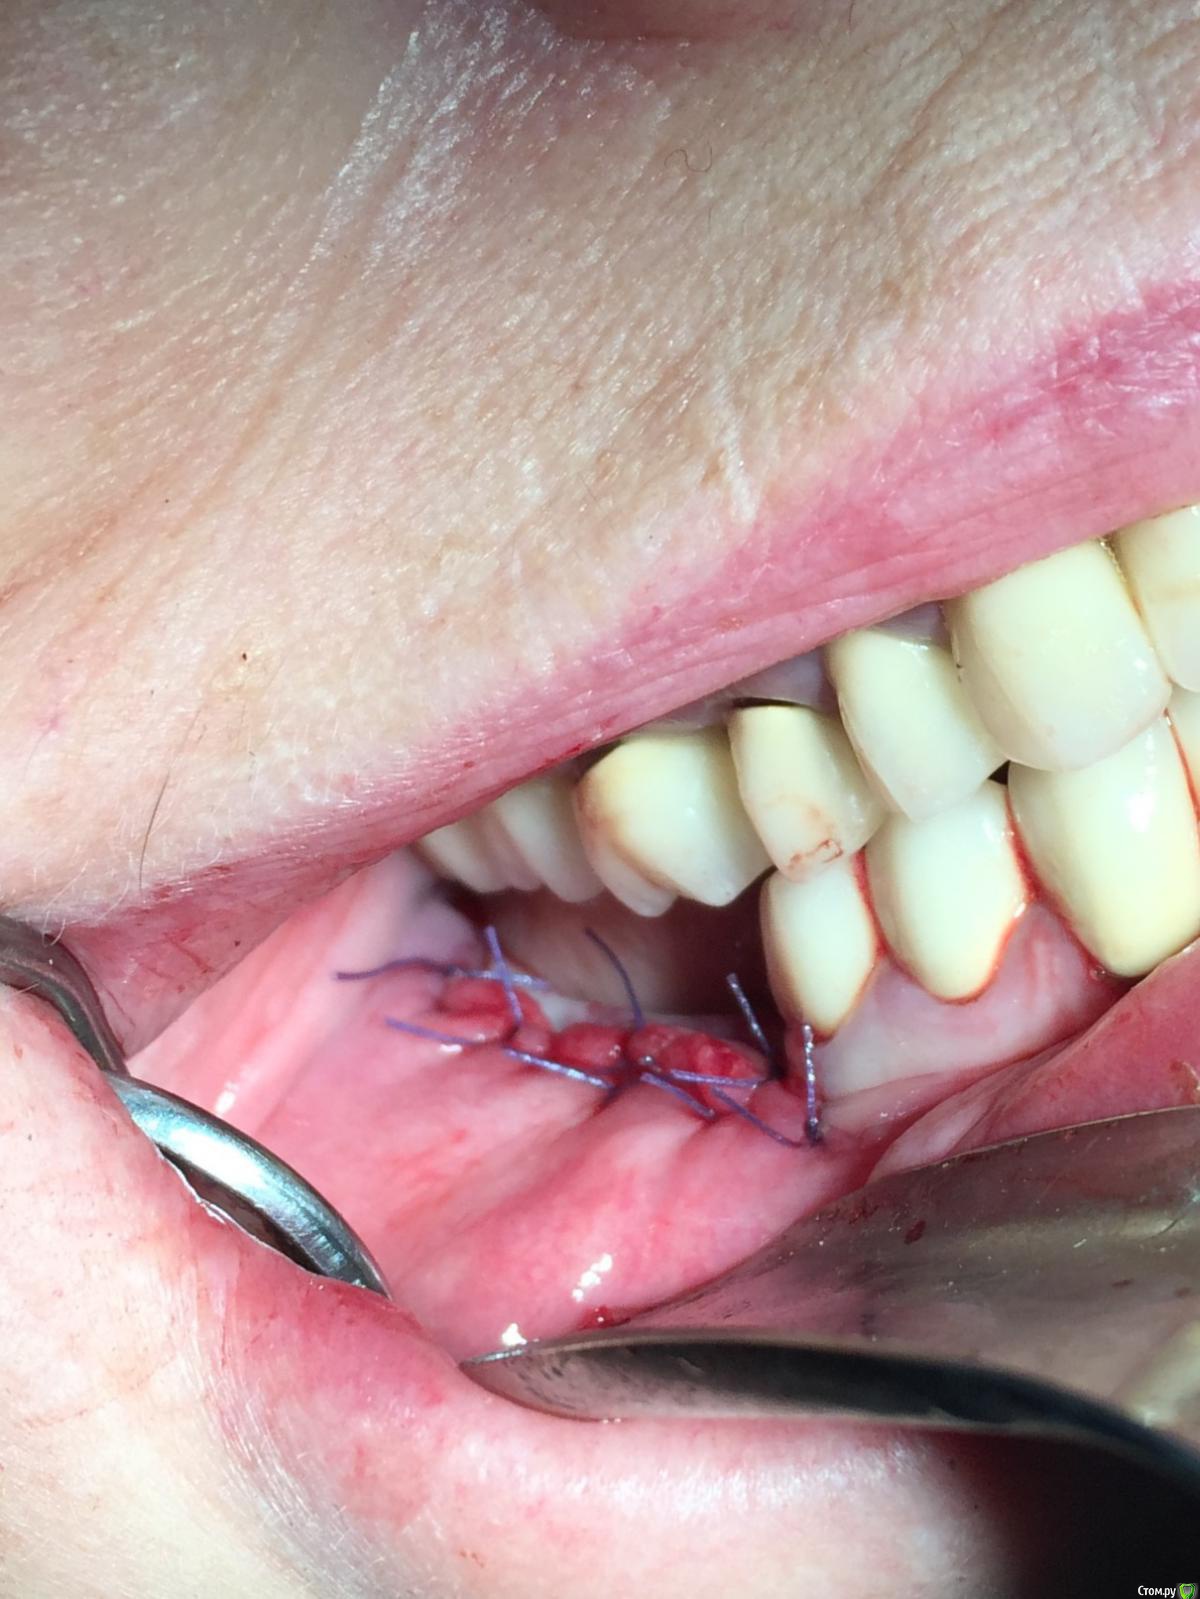

Популярный пост Глеб Митрофанов Опубликовано 22 октября, 2015 Популярный пост Поделиться Опубликовано 22 октября, 2015 (изменено) Горизонтальное расщепление Изменено 22 октября, 2015 пользователем Глеб Митрофанов 26 Ссылка на комментарий

Глеб Митрофанов Опубликовано 22 октября, 2015 Автор Поделиться Опубликовано 22 октября, 2015 Ну вертикально же пропилы есть, да и подняли вертикально) ваш первый подобный кейс? Как ощущения?)))))) , вертикальные пропилы есть , но остеотомия горизонтальная . Кейс первый , ощущения от того , что сделал это конечно переполняют эмоциями , впереди вторая сторона . Учту опыт первой Ссылка на комментарий